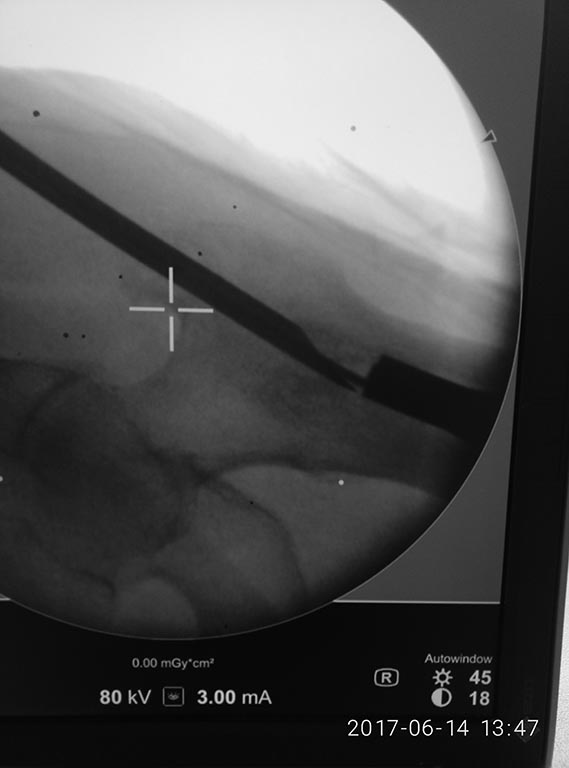

Доброе утро коллеги!фикшен с бедра удалили, сидел очень плотно.

На ортопедическом столе уложили, ногу согнули, как на ретроградное бедро, артротомия, релиз 4-главой, увеличили обьем движений. Далее попытка выбить плечевым, голенным штифтом не сильно имела успех. Стоял на своем. Проксимально по направителю рассверлили канал развертками 11,12. В итоге взяли 11 фемор санатметал, несколько ударов, и он вылетел из бедра!